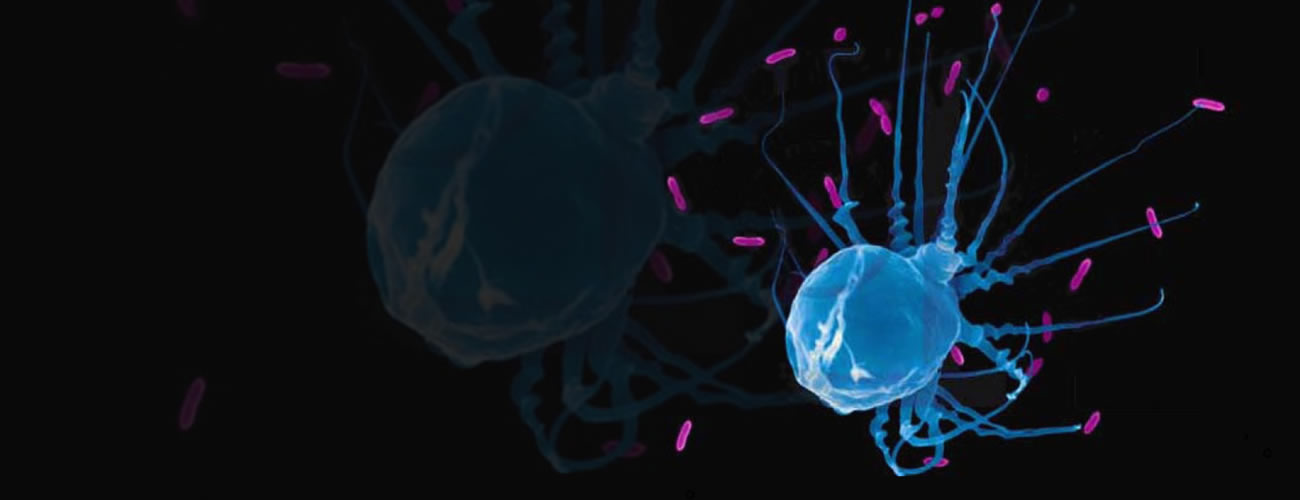

91吃瓜 医学标本馆是融医学多学科资源于一体的现代化医学标本博物馆,目前主要由标本馆展区、医学模拟中心、志愿遗体捐献登记接受站与志愿者服务基地三大模块组成,占地面积5000多平方米,馆内收藏的医学标本数量丰富、种类齐全,是91吃瓜 医学教育发展近150年的历史缩影与历史见证。

医学知识荟萃